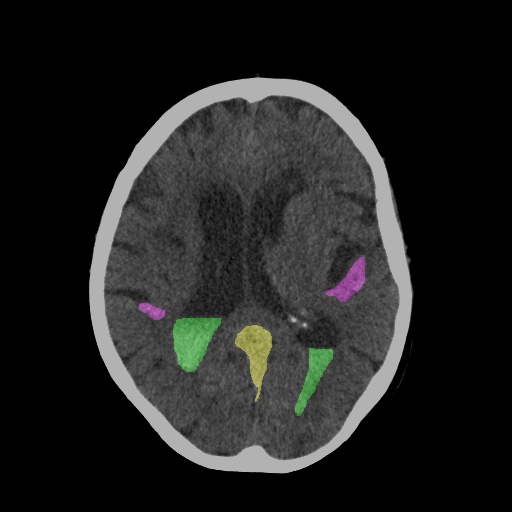

CT Scan After Diagnosis with Segmentation

Hemorrhage Segmentation

Segmentation & Volumetry

Precisely segments the hemorrhage area to calculate its volume, a critical biomarker for patient prognosis.